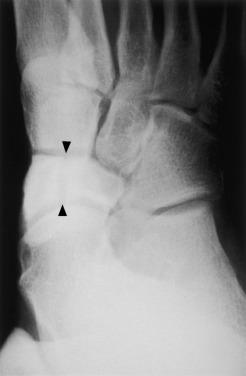

Imaging

Stress fracture of the tarsal navicular is often overlooked due to radiograph’s poor sensitivity (33%). An anteroposterior view of the foot can show: sclerosis of the proximal border of the navicular; a short first metatarsal; metatarsus adductus and hyperostosis; and stress fracture of the second, third, and fourth metatarsals. Most fractures are linear, lie in the middle third of the navicular, and can be complete or partial. Oblique or supinated radiographs can be useful ( Fig. 5.2 ).

Fig. 5.2, An oblique radiograph of the tarsal navicular demonstrates a stress fracture.